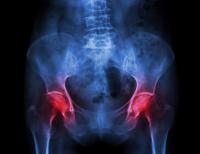

L’arthrose de hanche ou coxarthrose est l’usure du cartilage de l’articulation de la hanche.

arthrose de la hanche usure du cartilage de la hanche usure de l'articulation